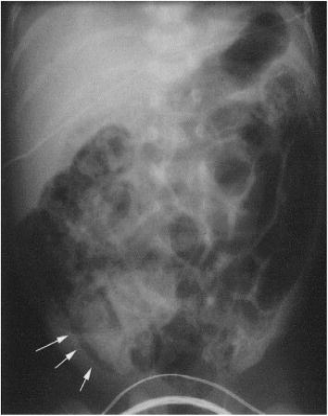

NEC